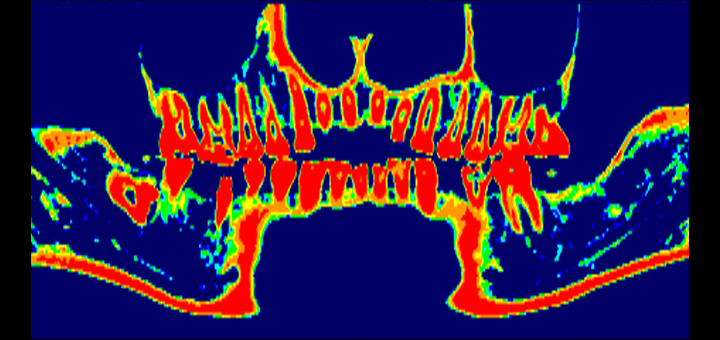

1. 正確に骨質を把握

他の歯科用CTは歯やあごの骨を立体的に把握することはできるものの、骨質(硬さ)について正確に把握することはできません。

一方で、当院の歯科用CTは骨質(硬さ)を正確に計測できるため、骨質(硬さ)を事前に把握しておくことが重要であるインプラント治療に特に有効です。

軟らかいあごの骨